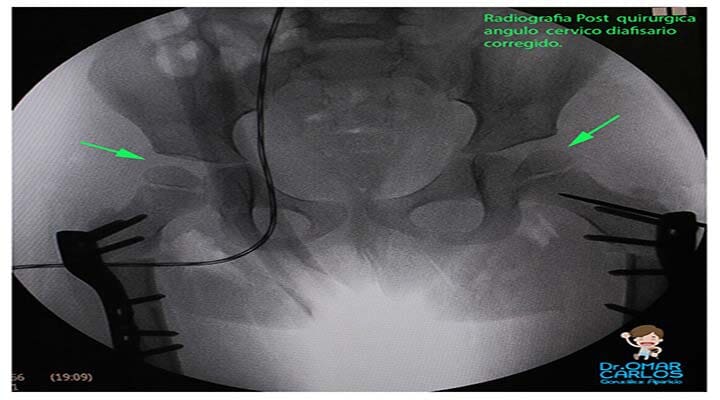

- Trastornos de la cadera (displasia de cadera, luxación congénita de la cadera, enfermedad de Perthes, epifisiolistesis, etc.)

- Cirugía de cadera y rodilla